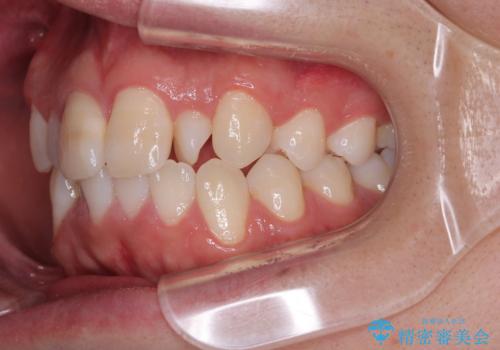

- 「上下の前歯がガタガタしているのが気になる」とのことで来院された患者様です。

上下顎前歯部に叢生(歯の重なり・ガタつき)を認め、見た目だけでなく、歯磨きのしにくさも気にされて来院されました。

インビザライン(マウスピース矯正)とワイヤー矯正のどちらが良いか悩まれていました。